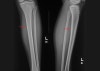

피로골절 감별을 위해 AP & Lateral view 검사를 시행합니다.

X-ray : 정강이 통증(Shin splints)